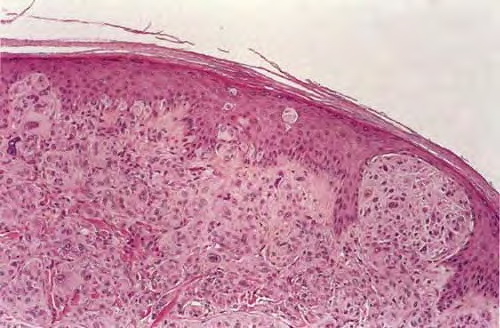

metastasis